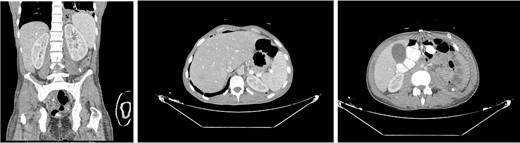

A 32-year-old male with no known medical history presented to the emergency department complaining of a high-grade fever of up to 40°C with rigors, intense hiccough, and back pain started four days prior. The patient reported a long-standing intravenous drug use (IVDU). Upon arrival, he was febrile (T: 41°C) and tachypneic (24 breaths/minute), the following vital signs were: heart rate 134 bpm, blood pressure 116/73 mmHg, oxygen saturation 94%. Examination of the abdomen revealed tenderness in the left iliac fossa and an abscess was observed in the left inguinofemoral region. Laboratory investigations revealed a leukocytosis of 12.300/mm3, elevated inflammatory markers (C-reactive protein of 19.24 mg/dl), and procalcitonin of 39 ng/ml, whereas the rest of the laboratory parameters were within normal limits. The microscopic urine analysis was normal. Blood cultures were obtained from separate venipuncture sites, and subsequently, we began intravenous fluid administration. Among the possible diagnoses, retroperitoneal abscess was prioritized due to clinical findings as well as because the patient reported several femoral vein punctures for drug injection. To set the diagnosis, the patient underwent a CT scan with IV and oral contrast. CT scan revealed swelling of the left femoral groin with the presence of a retroperitoneal abscess expanding through the left iliopsoas muscle to the perirenal space and left hemidiaphragm, which resulted in small left pleural effusion and infiltrates in the left lower lobe (Fig. 1).

CT images of the abdomen (venous phase) revealed a protruberance in the left inguinofemoral region extending into the retroperitoneal space, progressing as a perirenal abcess, spreading to the left sub-diaphragmatic region and causing an air-fluid level and an infiltrate in the lower lobe of the lung.